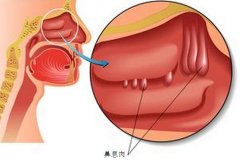

鼻息肉是有什么原因引起的

鼻息肉属于鼻部的一种常见疾病,鼻息肉对患者的生活、工作都有的影响,降低了患者的生活治疗,给患者带来了不少烦恼。为什么鼻子里面会长息肉,是由什么原因引起的呢? 鼻息肉示意图 鼻息肉是由什么原因引起的 就目前... [详情] 文章日期 :16-11-05